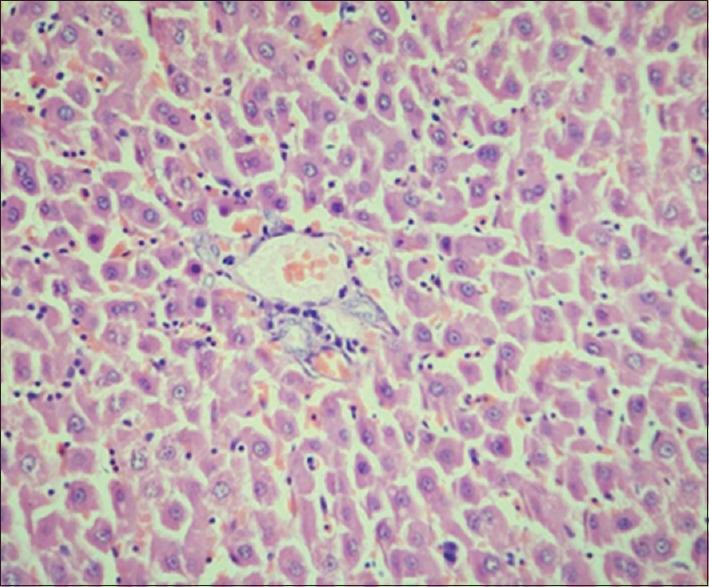

Oral submucous fibrosis was induced by submucosal injection of arecoline in the buccal mucosa. Arecoline hydrochloride at a dosage of 10 mg/kg was injected into the submucosa of right buccal mucosa in experimental animals over a period of 3 months on every alternate day. After which, right buccal mucosa, gastrointestinal tract organs like stomach, large intestine, small intestine and liver were dissected, subjected to histopathological evaluation of the healthy and experimental Wistar rats were subjected to histopathological evaluation.

On histological evaluation, OSMF was seen to affect Wistar rats showed significant changes in oral mucosa, decrease number of goblet cells in the small intestine as well in the large intestine and deranged hepatocytes. These marked changes indicated a definite effect on the gastro intestinal system by arecoline.